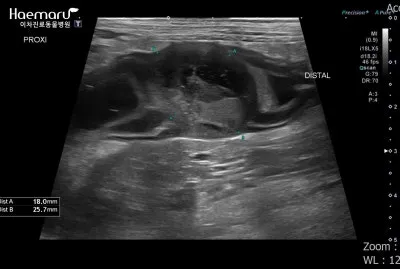

감염성 복막염은 주로 다른 장기의 염증이 확산되면서 발생해요. 예를 들어, 심한 췌장염이나 담낭염이 주변 복막으로 번지는 경우죠. 이런 경우엔 원발 질환 치료와 함께 복막염 관리를 동시에 해야 해서 치료가 더 복잡해집니다.